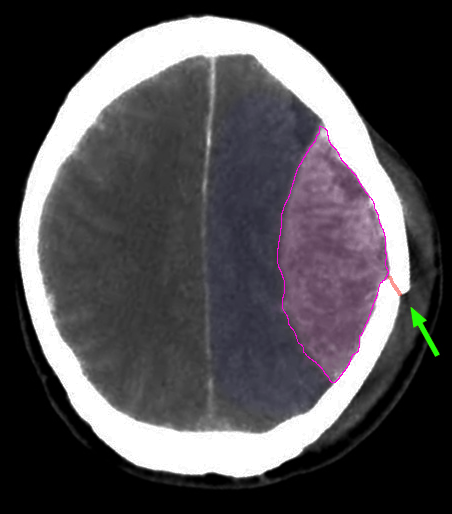

Epidural

Επισκληρίδιο αιμάτωμα (μώβ) κα κάταγμα κρανίου (πράσινο βέλος).